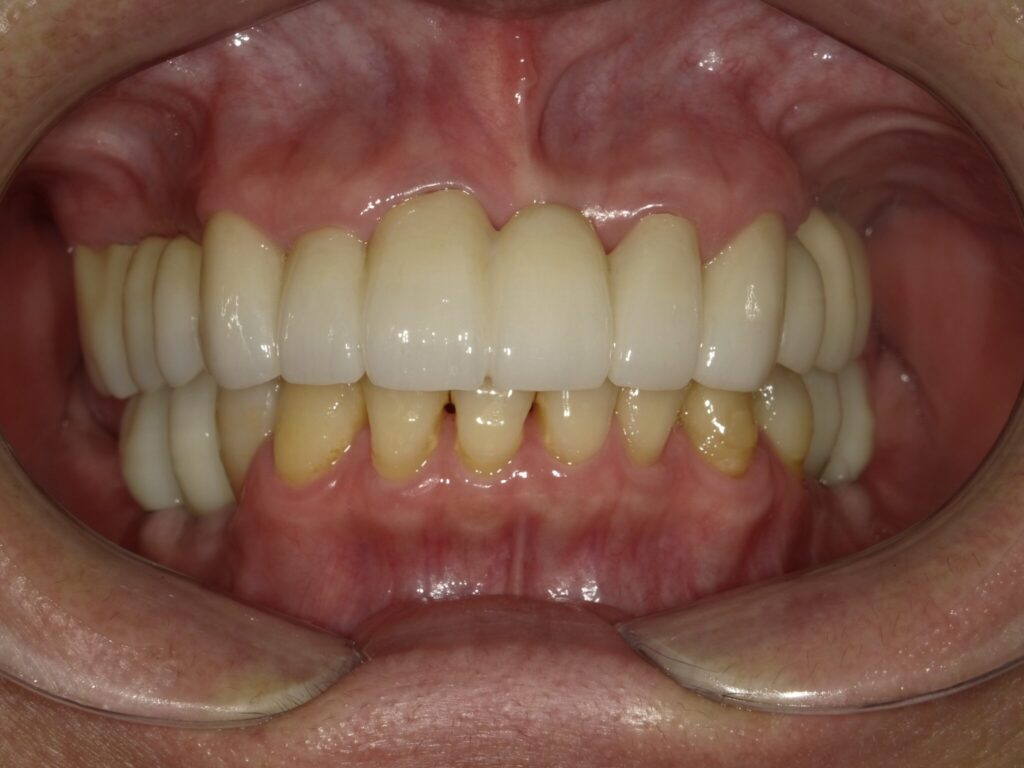

インプラント埋入(右上4・6,左上4・6,右下6,左下6) ジルコニアBr(右上3―左上3) ジルコニア(右下5,左下5) …続きを見る